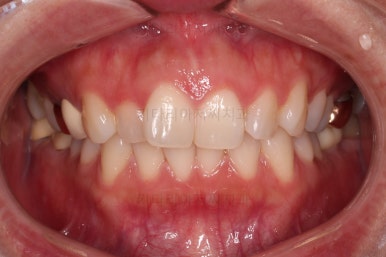

오늘 부산부분치아교정 키다리아저씨치과에서 소개해 드릴 환자분은 앞니가 삐뚤고, 토끼처럼 나와있다고 교정치료를 원하셨던 분입니다.

웃을 때 모습에서 앞니가 조금 삐뚤어 미적으로 좋지 못하고, 특히나 대문니가 더 튀어나와 강조되어 보이고 유달리 커보이는 효과까지 주네요.

전후 사진을 비교해 볼게요.

6개월만에 부산부분치아교정 완료했어요.

치열도 가지런해졌고, 웃는 모습도 매우 좋아졌네요.